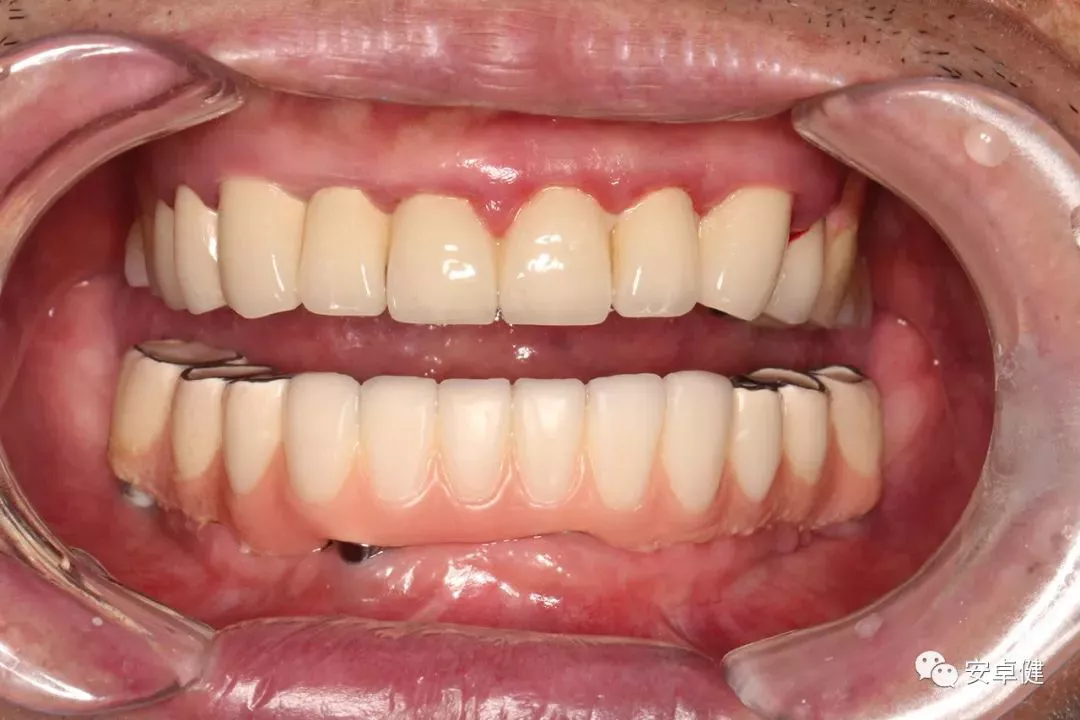

最终修复后8个月

戴牙后8个月复诊正面咬合照

• 随访可见患者口腔卫生状况可,牙龈无红肿;

• 下颌修复体状态良好,无修复体机械并发症;

• 种植体基台稳定性良好,无松动;

• 种植体无松动,周围无红肿、溢脓及疼痛表现;

• 正中、前伸及侧方咬合检查可见咬合印记分布均匀,咬合关系良好;

• 患者反映日常使用良好,舒适性佳,满意度高。